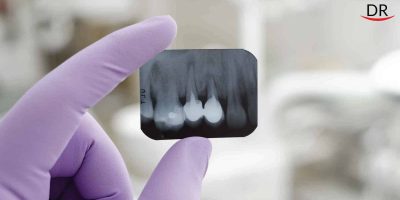

VistaScan Image Plate Scanner

VistaScan The conventional x-ray development and it’s introduction in the field of dentistry has been the cutting ...